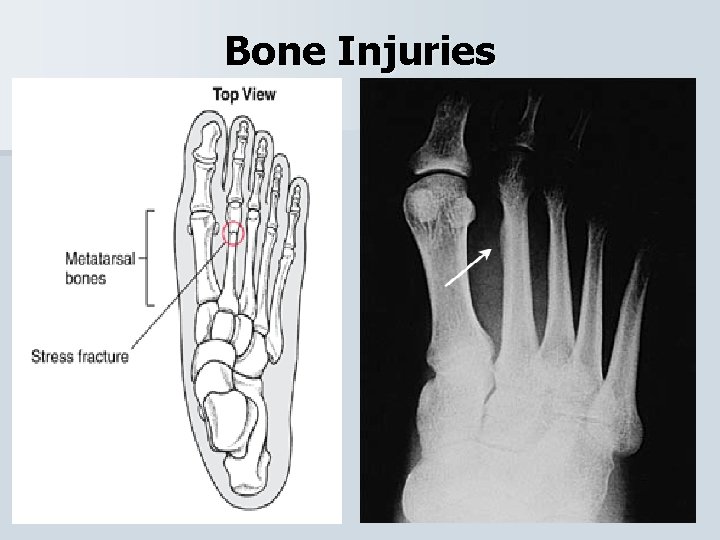

Bone Injuries Stress Fx • Most commonly occur to the tibia, fibula, and metatarsals. • Caused from repetitive stress (running). • Athlete will experience pain and swelling and the pain will be more intense at night and following activity. • X-Ray & Tuning Fork